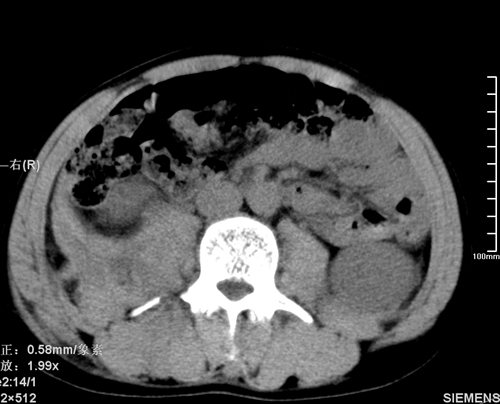

以下是引用qiushi在2008-3-28 12:00:00的发言:[br]腹膜后血肿,所见腰椎横突骨折.[br]建议上传骨窗、腰椎扫描.

以下是引用tao772在2008-3-28 12:29:00的发言:[br]右侧腹膜后积血,右侧腰大肌挫伤,右侧部分横突骨折. 肾脏最好报一下挫伤,必要时增强。